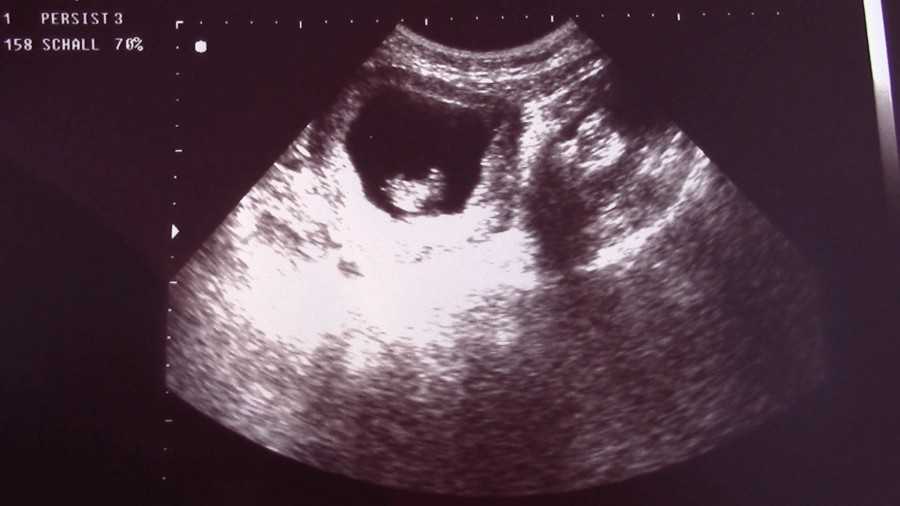

Также показано ультразвуковое исследование плода. Процедура УЗИ позволяет определить срок беременности, толщину плаценты, а также общее состояние яичников и пуповины.

На УЗИ плода на 9 неделе определяется толщина плаценты и общее состояние пуповины. При помощи допплера, будущая мама может отметить частоту сердечных сокращений малыша. Хотя многие внутренние органы уже достаточно развиты, это не всегда можно увидеть на УЗИ на 9 неделе.

Внутренние органы крохи еще могут выступать в виде пупочной грыжи, но нет повода для беспокойства, ведь это совершенно нормальное явление.

На УЗИ на данном сроке обязательным является общая оценка состояния яичников.

УЗИ на сроке 9 недель